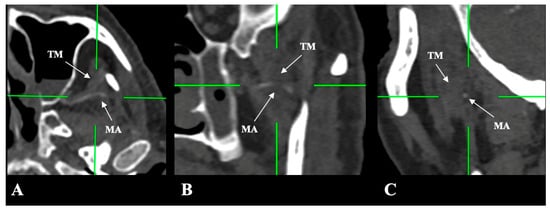

- Medial (deep) to the LPM: Identified in 148 sides (29.6%), best appreciated on axial and coronal reconstructions (Figure 3).

- Intramuscular (transversing the LPM fibers): Found in 31 sides (6.2%), clearly depicted in all planes (Figure 4).